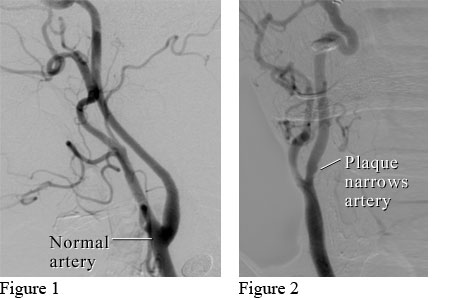

Here's what plaque buildup looks like in this angiogram of a carotid artery:

Plaque can form where arteries were damaged. Besides causing blockages, flakes of plaque can break away and travel to the brain. Or the plaque can rupture, allowing blood-cell fragments (platelets) to accumulate and possibly form blood clots.